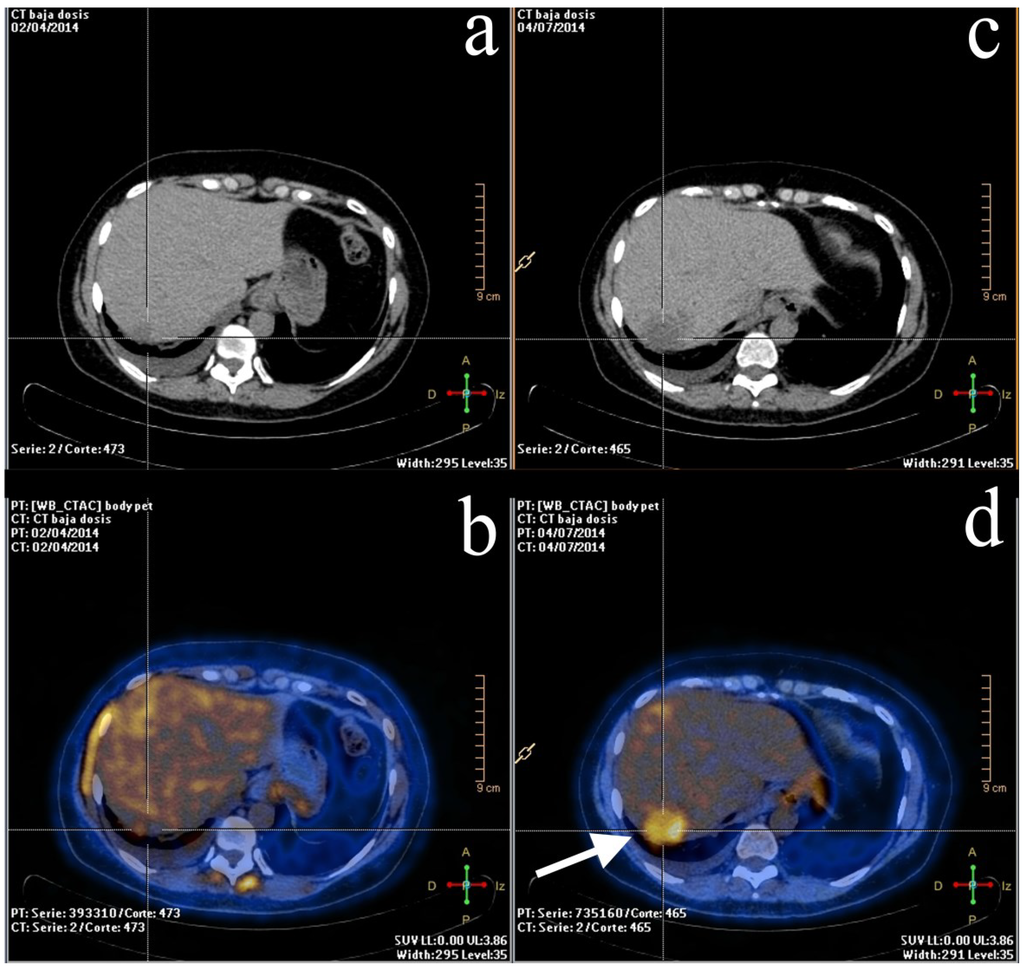

2.2. Staging and Re-Staging

2.3. Treatment Response Evaluation